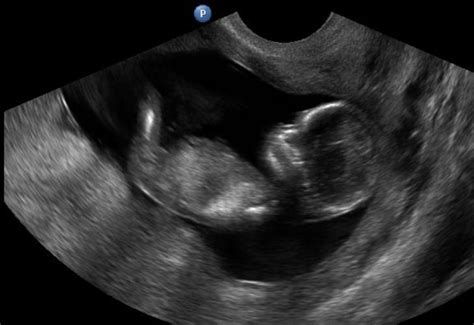

Az ötödik várandóssági héten hüvelyi ultrahanggal a petezsák, amely később méhlepénnyé alakul, már látható. Ebben a korai szakaszban a kezdődő élet még rendkívül sérülékeny. Emiatt sok nő megvárja a 12. hetet.

Mik lehetnek a terhesség jelei? - Feszülő, érzékeny mellek. - Korai terhesség jelei között tartjuk számon és akár az 1. héten is jelentkezhet. - fáradékonyság. Akár egyik pillanatról a másikra is jelentkezhet. - Akár már az 5. héten megdobbanhat a drága kicsi szíve. Hát nem csodálatos? Az élete kezdetét vette. Hüvelyi ultrahangon még csak a petezsák látható, az embrió még nem. Ilyenkor minden kismama megijed, mikor a vizsgáló orvos azt mondja, hogy nem lát elő magzatot. Azon kívül, hogy a méhen kívüli terhesség kizárható, más értelme nincs ilyen korán vizsgálatra menni. 8-10. héten menj először nőgyógyászhoz. Akkor már képen is fog tudni neked adni a kicsi életről.